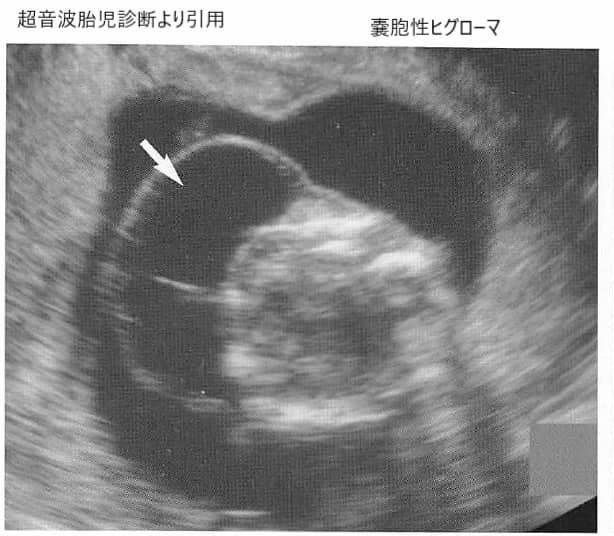

嚢胞性ヒグローマ(のうほうせいひぐろーま)は、通常、赤ちゃんの首や頭に現れる異常な構造で、NTと同じく超音波(エコー)では黒く抜けて見えます。

上のエコー写真は後頭部の約1/3をしめる厚さ1センチの皮膚の肥厚と皮下の嚢胞状の局所的な液体貯留(黒く抜けているところ)が複数あり、これが肥厚の原因となっていることがわかります。